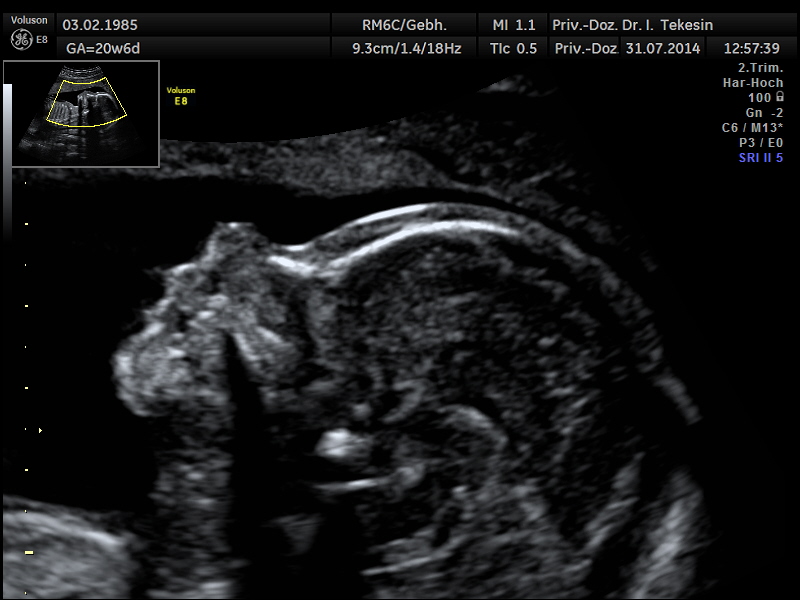

Die Ultraschalluntersuchung ist ein bildgebendes Verfahren, das nach heutigem Kenntnisstand selbst bei wiederholter Anwendung keine Schäden bei Mutter und Kind verursacht. Eine Ultraschallfeindiagnostik können wir Ihnen optimal zwischen der 20. und 22. SSW anbieten.

Eingehende Ultraschalluntersuchung

Diese Untersuchung ist wesentlich umfangreicher als der gemäß den Mutterschaftsrichtlinien vorgesehene Ultraschall in diesem Zeitpunkt. Neben speziellen Geräten erfordert er auch große Erfahrung des Untersuchers.

Entscheidende Rolle bei dieser Untersuchung spielt die Lage des Kindes und die Stärke der mütterlichen Bauchdecken. Dabei betrachten wir alle darstellbaren Organe und Merkmale des Ungeborenen: das altersentsprechende kindliche Wachstum, die Fruchtwassermenge, das Aussehen und die Funktion aller sichtbaren Organe und die Lage und das Aussehen der Plazenta.

Profil in der 21. Woche

Profil in der 25 Woche